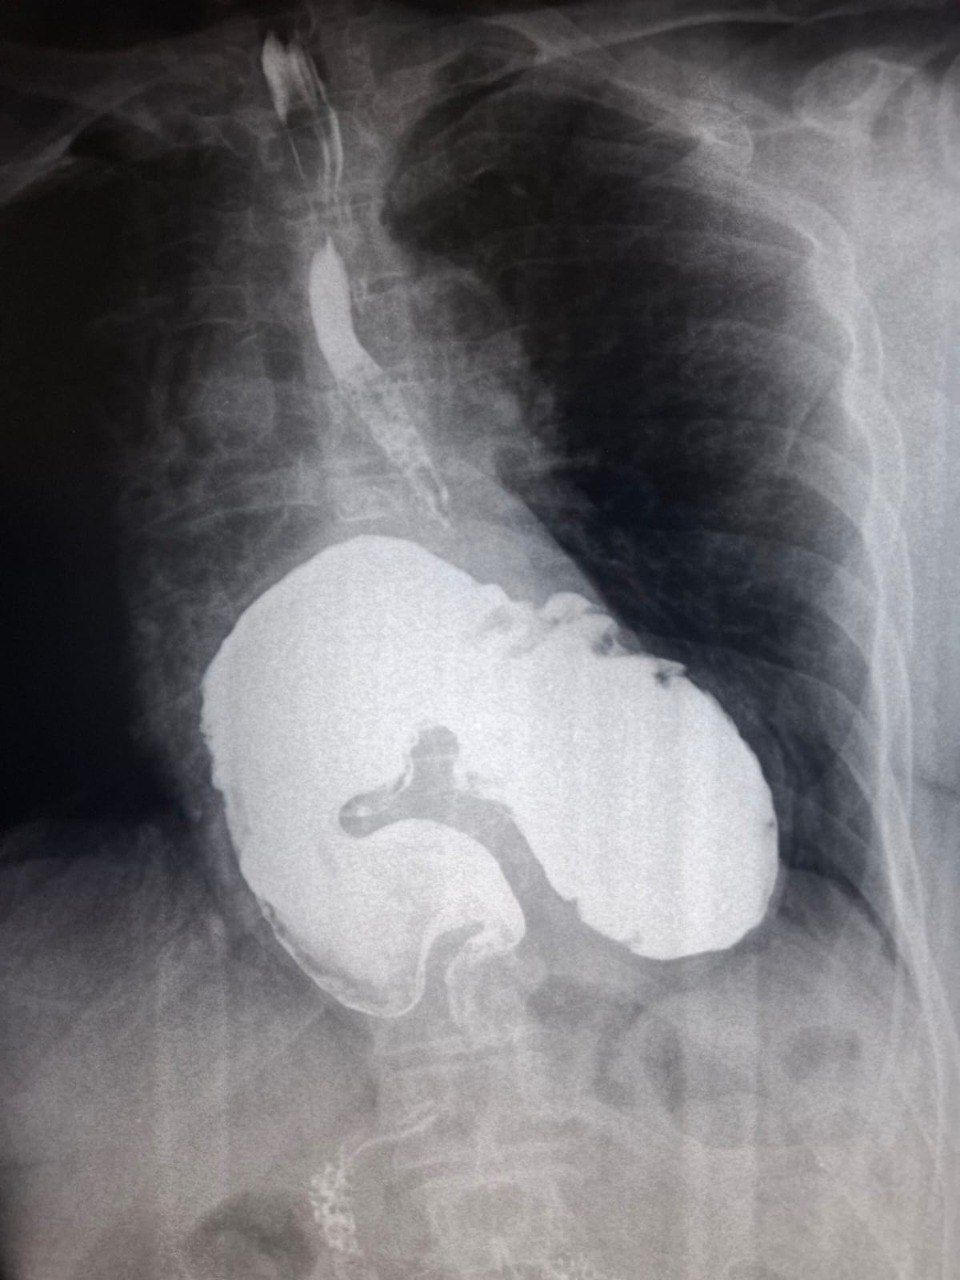

Краевая клиническая больница 2 🏥

Часто бывает, особенно у женщин, что за желудочными симптомамы скрываются проблемы с сердцем. Об этом мы писали здесь. Но иногда бывает и наоборот: жительницу Краснодарского края лечили кардиологи, а проблема оказалась с пищеводом. Причина недомогания обнаружилась случайно — во время стандартной рентгеноскопии пищевода, желудка и 12-перстной кишки с контрастом. И оказалась она неожиданной как для врачей, так и для самой женщины. Рентгеноскопия выявила гигантскую грыжу пищеводного отверстия диафрагмы в сочетании с дивертикулом нижней трети пищевода. Эти состояния могут долгое время развиваться бессимптомно или маскироваться под другую патологию, например, сердечную, — рассказали специалисты краснодарской Краевой клинической больницы № 2 в телеграм-канале стационара. После диагностики пациентку направили на консультацию к хирургам, а потом госпитализировали на одно из отделений больницы, где она сейчас проходит лечение. Грыжей пищеводного отверстия диафрагмы называют увеличение в размерах естественного отверстия диафрагмы, через которое пищевод проходит из грудной в брюшную полость. Из-за этого за счёт разницы в давлении из брюшной полости в грудную могут смещаться части органов — например, пищевода или желудка. Симптомы, по которым можно заподозрить ГПОД, включают: боли и жжение в груди, проблемы с глотанием, изжогу, нарушения сердцебиения. Причём, эти симптомы обычно усиливаются в положении лёжа или при наклонах. «Доктор Питер». Доступно и достоверно о здоровье